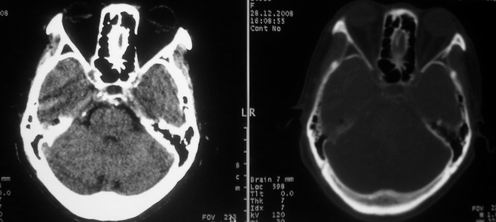

女,72岁,头晕。额骨有无问题。

额骨呈磨玻璃状增厚,考虑骨纤。

额骨呈磨玻璃状增厚,考虑骨纤

骨纤维组织异常增殖症又名纤维性骨炎,是一种以骨纤维变性为特点的骨胳系统疾病,是否为一真性肿瘤尚无定论。该病好友于儿童及青年,女性较多见,60%发生于20岁以前,偶见于婴儿和70岁以上老年人。男女发病为1∶2。80%以上表现为病骨区畸形肿胀;建议祥问病史,时间?